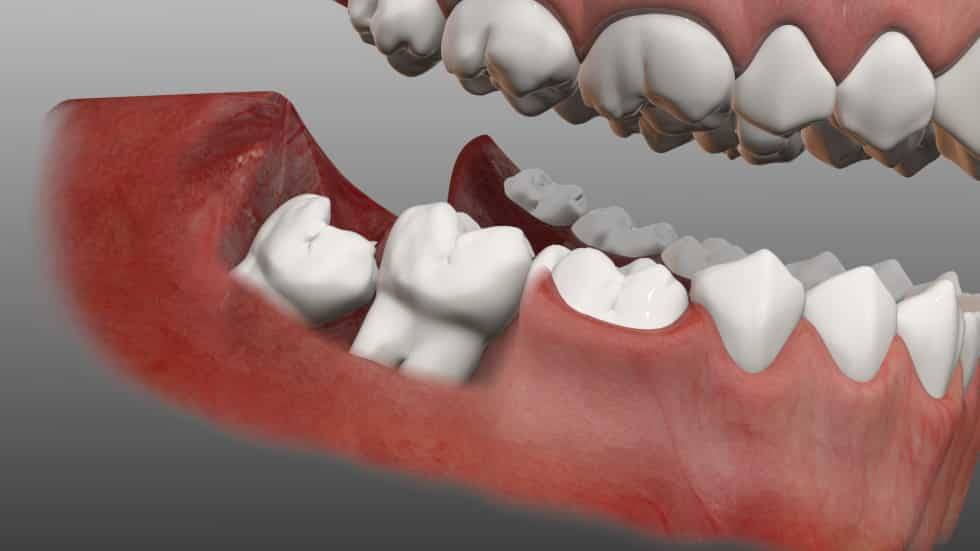

دندان عقل آخرین دندانی است که معمولاً بین سنین ۱۸ تا ۲۵ سالگی در انتهای فک رشد میکند. گاهی فضای کافی برای رویش کامل وجود ندارد و بخشی از دندان در زیر لثه یا استخوان گیر میکند. در این حالت، دندان عقل به دو نوع تقسیم میشود:

| دندان عقل نیمه نهفته | بخشی از دندان بیرون آمده، بخشی زیر لثه مانده | ممکن است باعث التهاب و گیر کردن غذا شود |

| دندان عقل نهفته | کل دندان زیر لثه یا استخوان گیر کرده | نیاز به جراحی تخصصی دارد |

هر دو حالت میتوانند دردناک باشند و در صورت بیتوجهی منجر به عفونت، آبسه و آسیب به دندانهای مجاور شوند.